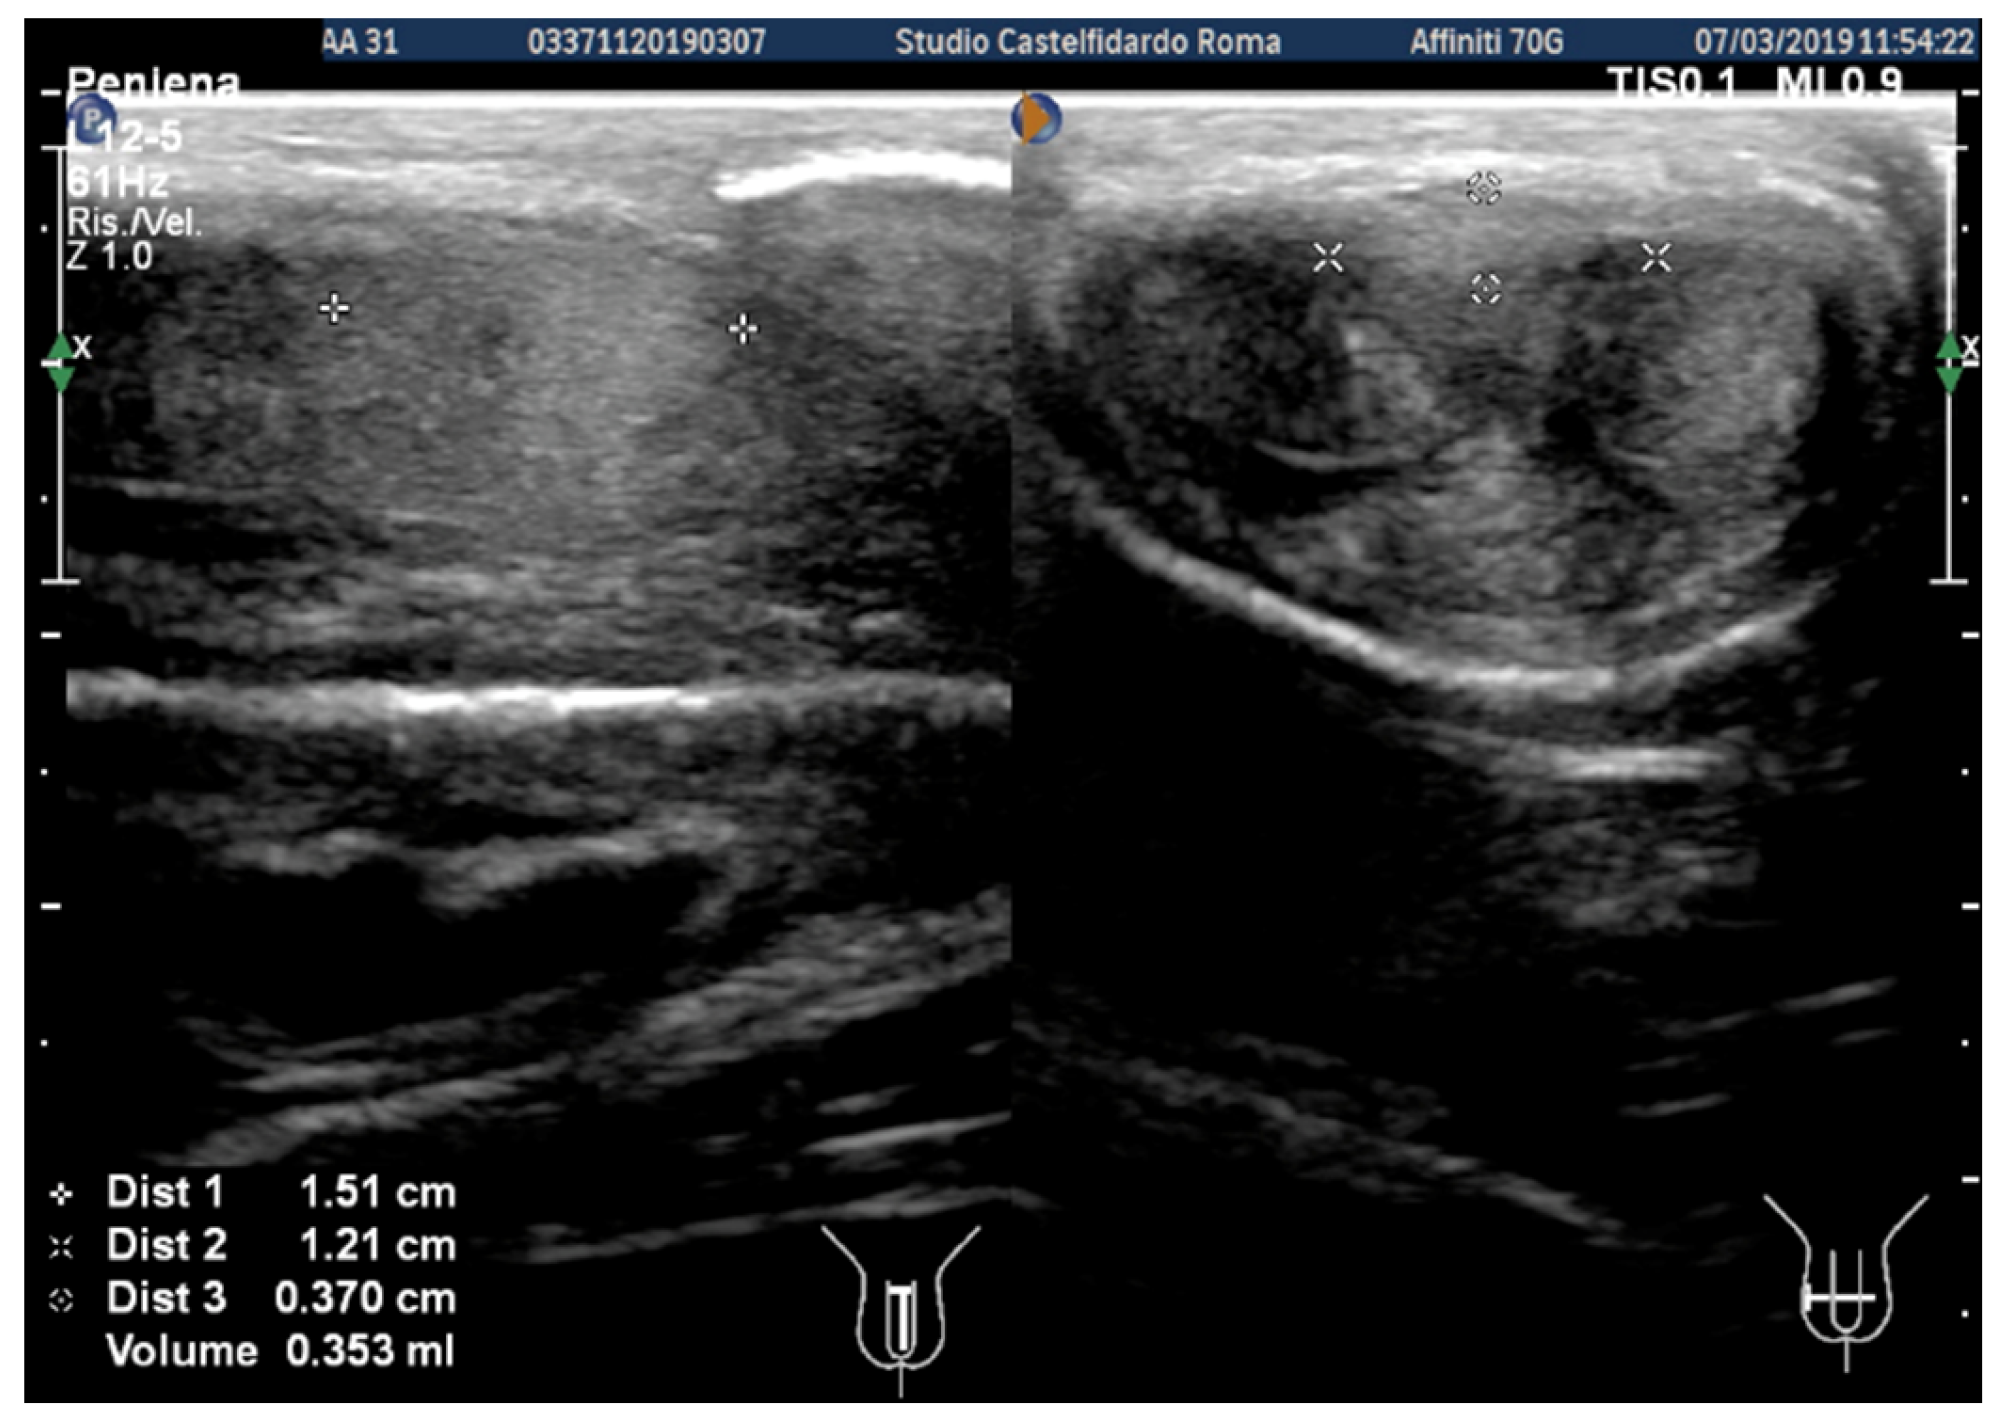

| 1 | 31 years | Chronic prostatitis and associated anxious and depressive state. | Distal third | (A) 15.1 × 12.1 × 3.7 mm volume = 353 mm3 (B) No plaque detected | (A) 10-degree ventral curvature + 15-degree left curvature (B) None | VAS score = 8 Pain disappeared after 12 months | 26 > 27 | 30 months | Orally: propolis 600 mg + bilberry 160 mg + silymarin 400 mg + ginkgo biloba 250 mg + L-carnitine 1000 mg + coenzyme Q10 100 mg + Boswellia 200 mg + Vitamin E 30 mg/daily/for 30 months + topically: diclofenac gel 4%/2× daily for 30 months Note: The patient refused periplaque penile injections with pentoxifylline |